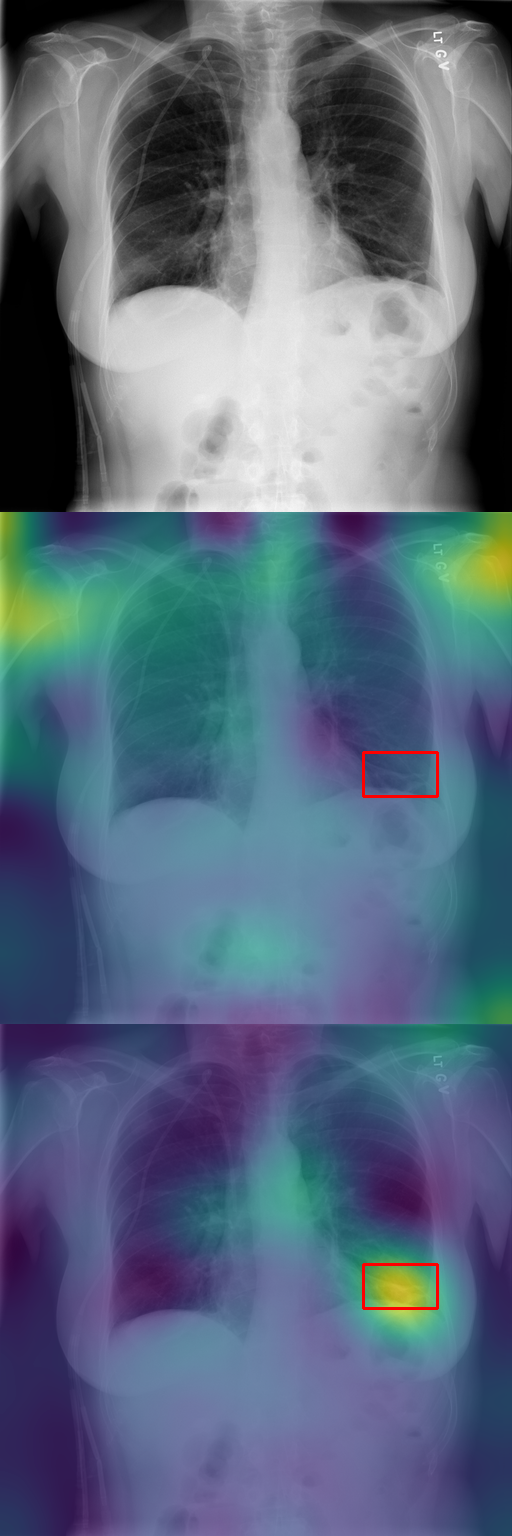

Effect of finetuning. Unsurprisingly, we found that finetuning the diffusion model on the dataset of interest was critical to the quality of our results. First, on a given image, finetuning changes the spatial distribution of typicality, prioritizing elements more correlated with the training labels (see Fig. 3(a)). Second, in Fig. 3(b), we show the most typical clusters identified before and after finetuning. The patches selected after finetuning avoid the biases in the training data of the base model and are more specific to the G ^3 dataset, identifying elements such as post-boxes. We also demonstrate this quantitatively in Section 5.2 for our application to X-ray images. Third, finetuning enables better translation between labels (see Sec. 5.1), as can be seen in Figure 3(c), allowing vegetation, roads, road tracks, and utility poles to be translated consistently across the class labels in the parallel dataset (which can be found in the supplementary material).

Our typicality score allows us to explore two different applications. First, in Section 5.1, we translate geographical elements across locations and mine typical translations. Then, in Section 5.2, we show how disease localization emerges from typicality when training to generate frontal X-rays of patients, of various diseases.

5.2 Analysis of Medical Images

In Section 4.2, we discussed how typicality helps find relevant patches for an input label. In this section, we test this idea on completely different images: X-rays of patients who may suffer from a combination of various thorax diseases. We finetune Stable Diffusion on the ChestX-ray8 dataset [46] containing 108,948 frontal-view X-ray images annotated with 14 single-word disease-name labels. Experts annotated a test set of 879 images with 7 diseases with rectangular regions of interest (ROI) for each disease. For each image, we compute typicality per latent feature, interpolate the resulting typicality to the input dimension, and blur the resulting typicality map for visualization. In Fig. 11, we show the resulting typicality maps together with the ROI annotation before and after finetuning. Finetuning clearly improves the localization. We quantify this effect by computing the area under the precision recall-curve [5] (AUC-PR) associated with the ROIs. As reported in Fig. 11, we see consistent improvement of this measure when finetuning the network (from 3.2% to 9.6%), ranging from +3.5% for Pneumonothorax (from 3% to 6%) to +14.6% for Mass (from 2% to 16.6%), which are respectively the least and most localized diseases. Similar to our other experiments, finetuning uses only image labels without localization supervision.